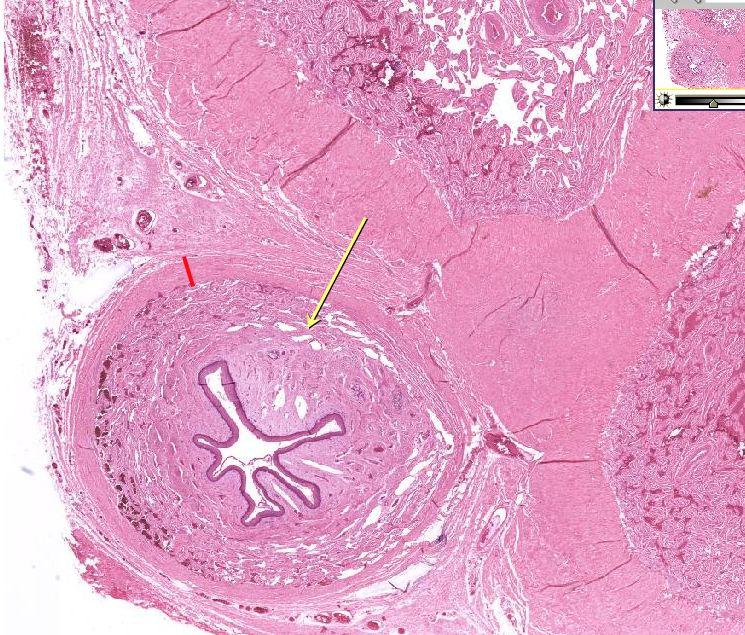

Anatomy of penis | Shaft cross section shows skin (S), darto …